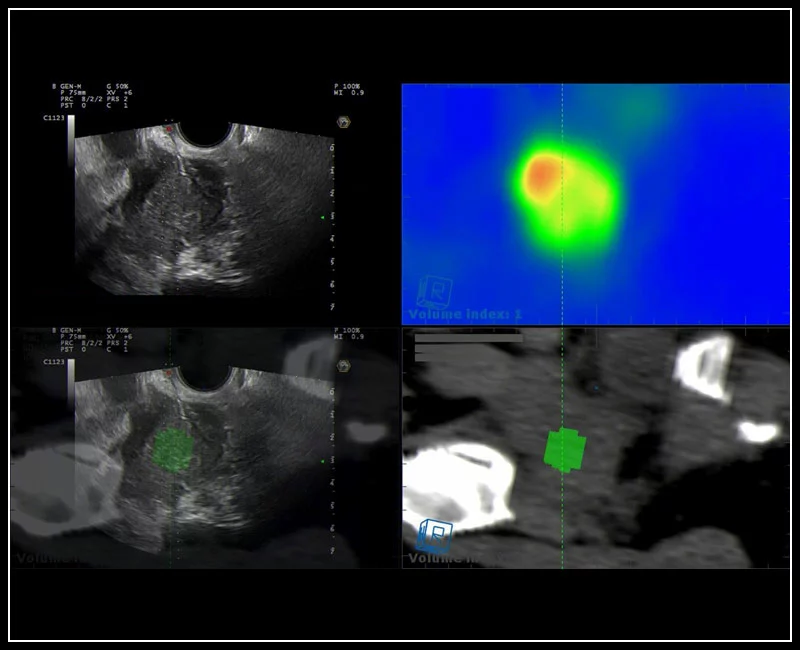

MyLab™E80 - Urofusion - TP Biopsy

MyLab™E80 - Urofusion - TP Biopsy